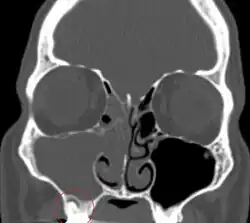

CT showing complete opacification of the right maxillary and right anterior ethmoid sinuses with associated involvement of the ostiomeatus.

Sinusitis is inflammation of the paranasal air sinuses. Odontogenic sinusitis is that which results of dental disease, most often resulting from prior dentoalveolar procedures, infections of maxillary dentition, or maxillary dental trauma.[6] Infections associated with teeth may be responsible for approximately 20% of cases of maxillary sinusitis.[7] The cause is usually a periapical or periodontal infection of a maxillary posterior tooth, where the inflammatory exudate has eroded through the bone superiorly to drain into the maxillary sinus. Treatment of the underlying dental disease is the first step in the treatment of odontogenic sinusitis, however recent a portion require endoscopic sinus surgery for successful resolution.[6] Once an odontogenic infection involves the maxillary sinus, it is possible that it may then spread to the orbit or to the ethmoid sinus.[7]